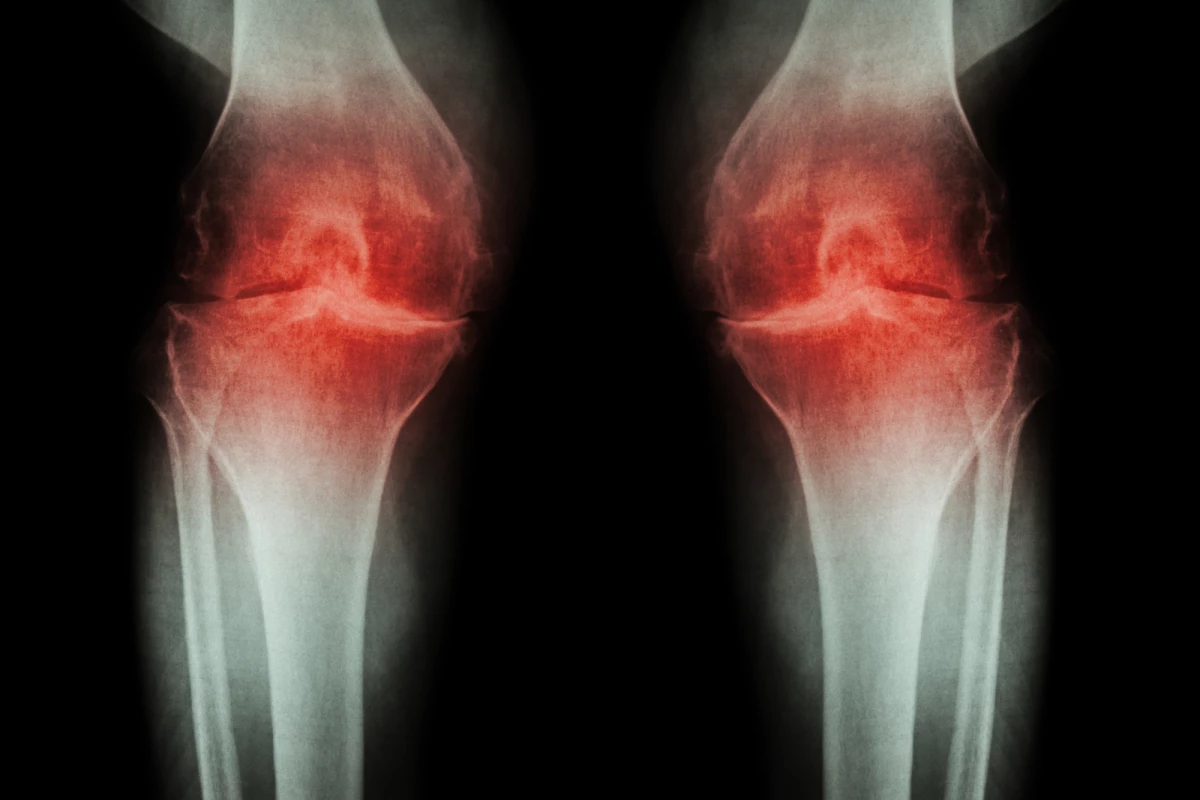

Osteoarthritis can be a debilitating disease, rendering regular movements painful. Researchers have now identified a signaling pathway that transmits this pain, with a study in mice finding that normal limb use returned after this pathway was blocked. The work could lead to new pain treatments for patients with osteoarthritis.

The disease begins as the cartilage in joints wears away, causing pain as bones increasingly rub against each other. Pain can be managed using over-the-counter medication or lifestyle changes, but can remain a problem as the disease progresses. To find better long-term drugs to manage chronic pain, scientists have been investigating the molecular pathways that communicate pain to the brain.